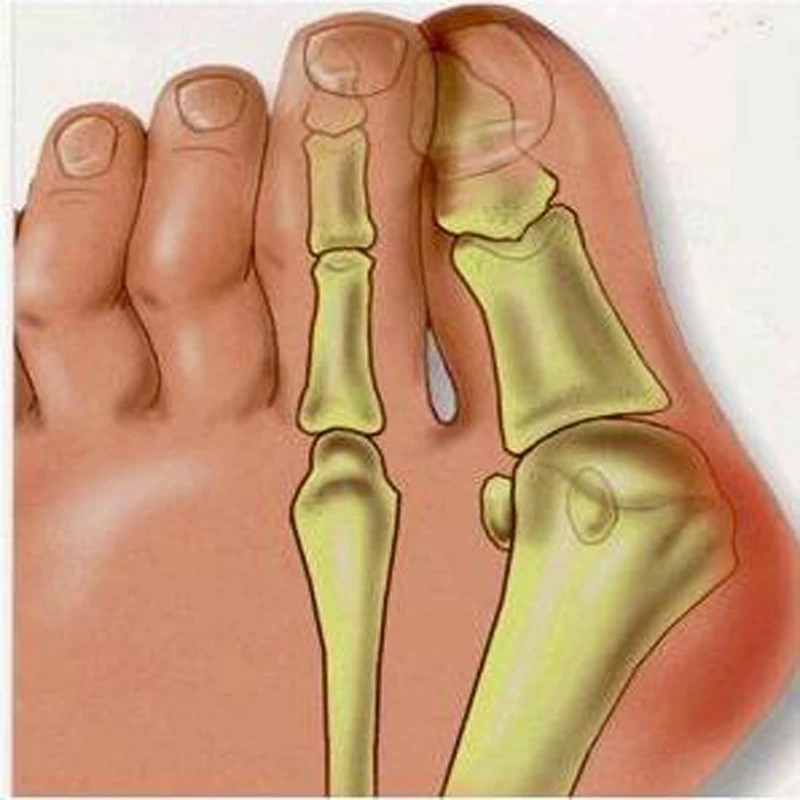

Экзостоз пальцев стопы

Экзостоз пальцев стопы 143 фотографий